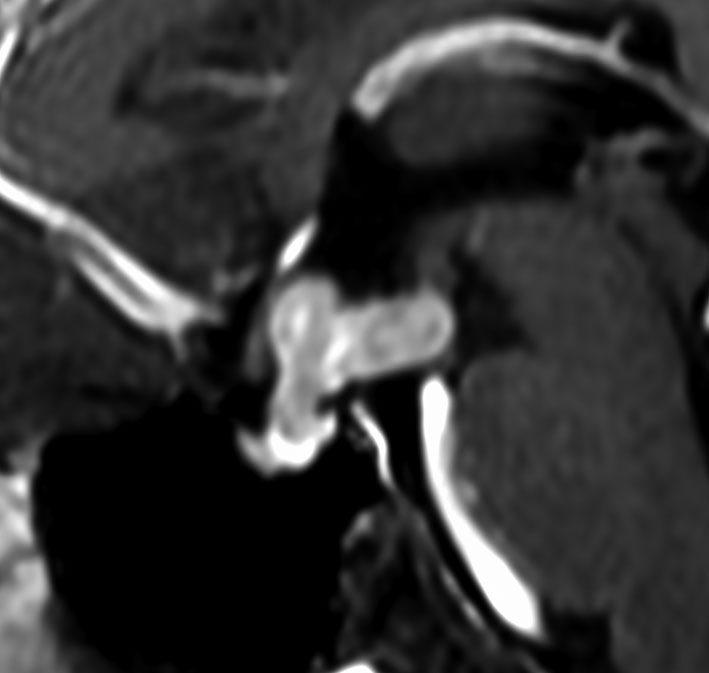

尿崩症にて発症した2年後にようやく小さなneurohypophyseal germinomaを発見された9歳女児例です。術前のT1強調画像では下垂体後葉のbrightnessが消失し,下垂体柄が腫大しています(左側)。ガドリニウムで腫瘍部分が増強されますが前葉よりは低信号となっています(右側)。経蝶形骨洞生検術で確定診断を得た後に,シスプラチンとエトポシドを1コース投与したところ腫瘍は完全消失しました。3コース後に24Gy12分割の放射線治療を加え再発はありません。残っていた下垂体前葉機能は治療後に少し改善しました。生検術では,トルコ鞍底を開けて下垂体後葉の下部を目標にして小さな組織採取をします。GHDがあっても前葉にはmassとしての腫瘍が無いと考えた方がいいでしょう。